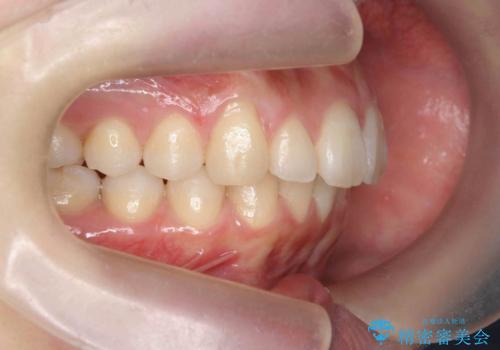

マウスピースで出っ歯感の改善

- 上の前歯が出ている感じを治したい、と矯正治療を希望され来院されました。

上顎歯列の突出感を改善すべくIPRを行い、下顎歯列を小さくすることで前歯の角度を大きく是正します、。

下顎歯列は元々前歯が1本少なく小さなアーチでしたが、下顎に合わせ上顎歯列もIPRを行い小さくすることで出っ歯感を大きく改善することが出来ました。